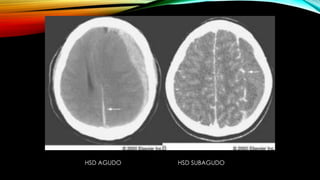

DIAGNÓSTICO DE HSD

• TAC craneal:

Agudo 1-3 dias Hiperdenso

Subagudo 4º dia- a 2-3 semanas Isodenso

Crónico > 3 semanas y < 3-4 meses Hipodenso similares a la

densidad del LCR

Despues de 1-2 meses Pueden ser lenticulares

(similares a los

epidurales) con

densidad > LCR y <

sangre nueva

HSD AGUDO HSD SUBAGUDO